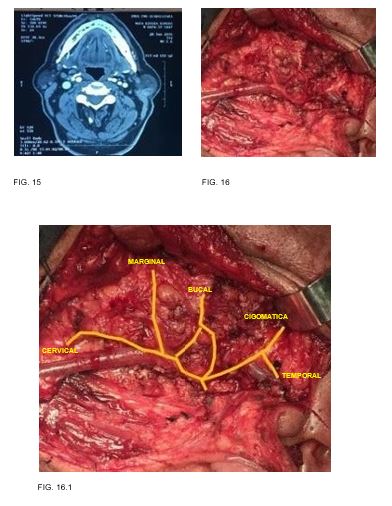

Caso 1: Masculino 49 años de edad, antecedente de tabaquismo e hipertensión, tumor parotídeo derecho de 5x3.5x2.5 pétrea. fue sometido a parotidectomía supraneural, resultando en melanoma maligno nodular con patrón sarcomatoide. (FIG. 1-2)

1

2

Caso 8: masculino de 59 años de edad, antecedente de diabetes mellitus y tabaquismo con tumor parotídeo izquierdo de 3cm en su eje mayor resultando en tumor de Warthin (FIG. 15-16)

9